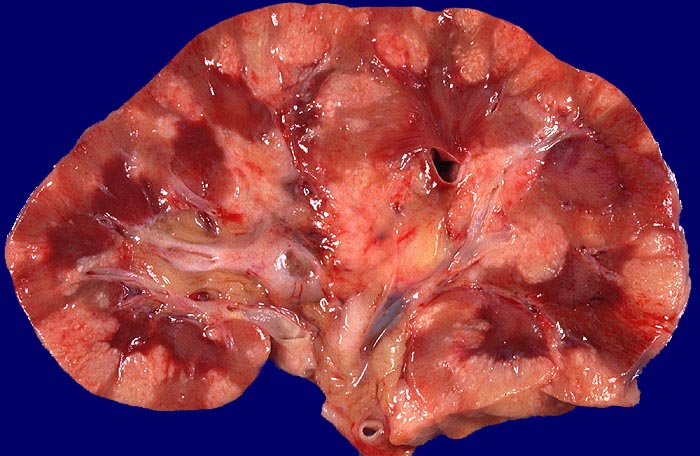

PathoPic – image database / PathoPic ID 353 - kleinzelliges Bronchuskarzinom: Metastasen

kleinzelliges Bronchuskarzinom: Metastasen

Topographie

Kleinzelliges Bronchuskarzinom bekannt seit 1 Jahr. St.n. Chemotherapie. Nikotinabusus.

Makroskopie